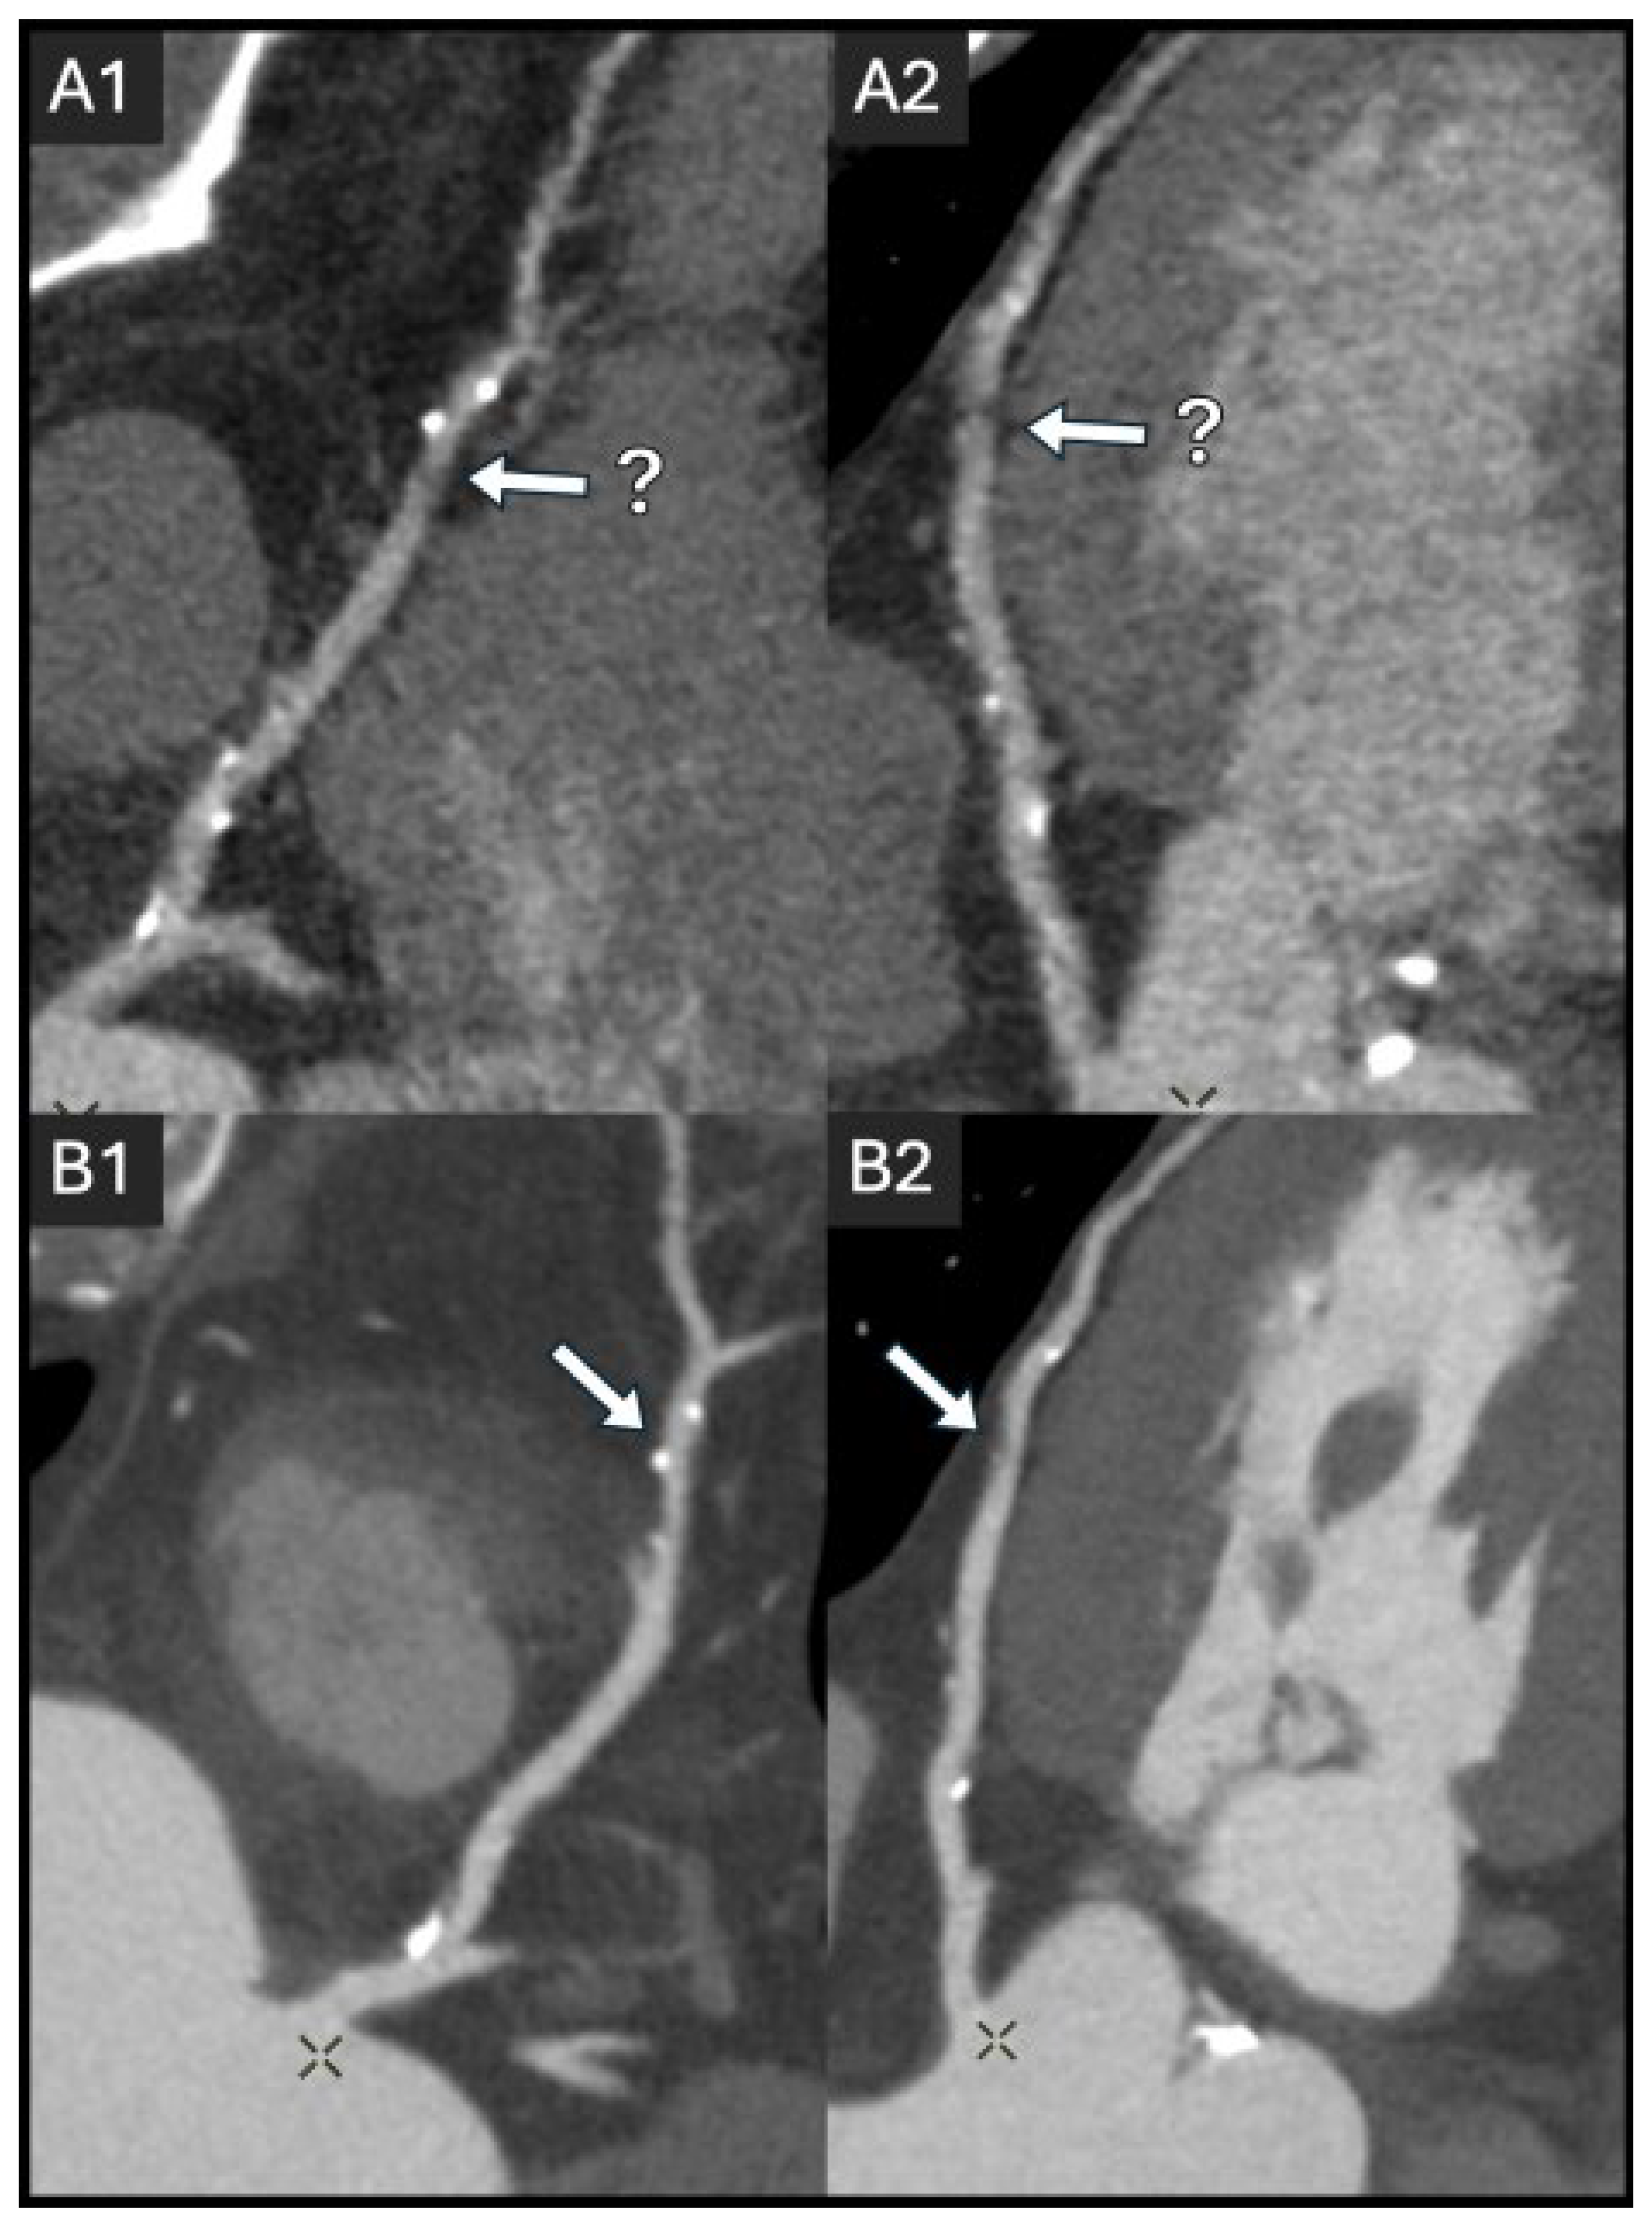

2.2. Coronary Lumen Attenuation

- Cademartiri, F.; Maffei, E.; Palumbo, A.A.; Malagò, R.; La Grutta, L.; Meiijboom, W.B.; Aldrovandi, A.; Fusaro, M.; Vignali, L.; Menozzi, A. Influence of intra-coronary enhancement on diagnostic accuracy with 64-slice CT coronary angiography. Eur. Radiol. 2008, 18, 576–583. [Google Scholar] [CrossRef]

- Fei, X.; Du, X.; Yang, Q.; Shen, Y.; Li, P.; Liao, J.; Li, K. 64-MDCT Coronary Angiography: Phantom Study of Effects of Vascular Attenuation on Detection of Coronary Stenosis. Am. J. Roentgenol. 2008, 191, 43–49. [Google Scholar] [CrossRef]